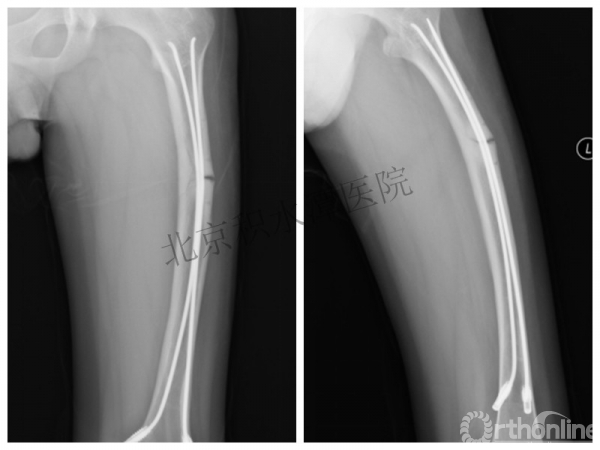

男孩 、5岁,初次骨折于2007年7月。

术后2年→再骨折→再次手术

取板后再骨折→TEN

TEN取出后2个月

闭合复位再固定加尾帽